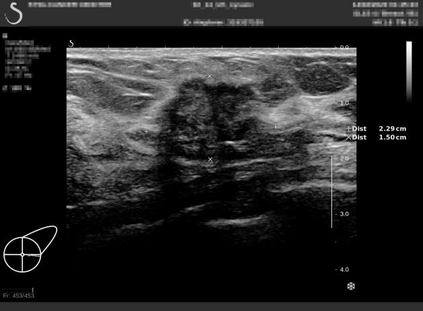

Ultrasonography is an important routine examination for breast cancer diagnosis, due to its non-invasive, radiation-free and low-cost properties. However, it is still not the first-line screening test for breast cancer due to its inherent limitations. It would be a tremendous success if we can precisely diagnose breast cancer by breast ultrasound images (BUS). Many learning-based computer-aided diagnostic methods have been proposed to achieve breast cancer diagnosis/lesion classification. However, most of them require a pre-define ROI and then classify the lesion inside the ROI. Conventional classification backbones, such as VGG16 and ResNet50, can achieve promising classification results with no ROI requirement. But these models lack interpretability, thus restricting their use in clinical practice. In this study, we propose a novel ROI-free model for breast cancer diagnosis in ultrasound images with interpretable feature representations. We leverage the anatomical prior knowledge that malignant and benign tumors have different spatial relationships between different tissue layers, and propose a HoVer-Transformer to formulate this prior knowledge. The proposed HoVer-Trans block extracts the inter- and intra-layer spatial information horizontally and vertically. We conduct and release an open dataset GDPH&GYFYY for breast cancer diagnosis in BUS. The proposed model is evaluated in three datasets by comparing with four CNN-based models and two vision transformer models via a five-fold cross validation. It achieves state-of-the-art classification performance with the best model interpretability.

翻译:超声波分析是乳腺癌诊断的一个重要常规检查,原因是其非侵入性、无辐射和低成本的特性。然而,由于其内在局限性,它仍不是乳腺癌的第一线筛选测试。如果我们能够精确地通过乳房超声图像诊断乳腺癌(BUS),它将是一个巨大的成功。我们提出了许多基于学习的计算机辅助诊断方法,以实现乳腺癌诊断/感官分类。然而,其中多数方法需要事先确定性能模型,然后对ROI内部的跨值进行分类。常规分类支柱,如VGG16和ResNet50等,可以在没有ROI要求的情况下实现有希望的分类结果。但是这些模型缺乏可解释性,从而限制了其在临床实践中的使用。在本研究中,我们提出了一个新的无乳腺癌诊断模型,在超声波图像中进行解释性特征描述。我们利用了先前的解剖学学学知识,即恶性肿瘤和良性肿瘤模型在不同组织层之间有着不同的空间关系,并提议采用状态解析法来编制这一先前的知识。拟议中的HOVer-Trans-Trading-Tradef-trainal Ex-deal-dealal-deal-deal-deal-degraphal-deal-deal-deal-deal-deal-deal disal disal-dal-dal-dal-dal-dal-deal-deal-dal-deal-deal-deal-dal-dal-dal-dal-dal-dal-dal-dal-dal-dal-dal-dal-dal-dal-I-dal-Iversal-dal-Ial-d-d-I-d-d-I-I-I-I-I-I-I-I-I-I-I-I-I-I-I-I-I-I-I-I-I-I-I-I-I-Ial-I-Ial-Ial-I-I-I-I-I-I-I-I-I-I-I-I-I-I-I-I-I-I-I-I-I-I-I-I-I-I-I-I-I-I-I-I-